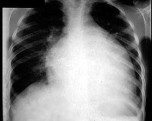

- [材料题] 男,24岁,反复胸闷气短4年,近1周加重,端坐时即感胸闷,伴咳嗽、下肢水肿,肝脏肿大。超声心动图示心脏扩大,室壁变薄,EF值20%,二尖瓣、三尖瓣中度反流。胸片如图所示。